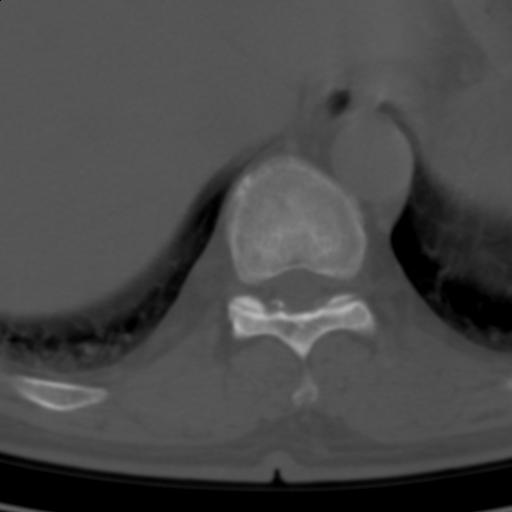

标题: CT25189:胸椎ct,请会诊! [打印本页]

标题: CT25189:胸椎ct,请会诊!

既往食管癌,现行ct检查!

仅见椎体退行性改变

中上段食道癌,椎体轻度退变。

椎体退行性改变,食管癌。

支持中上段食道癌,椎体轻度退变,必要时做ect。

支持中上段食道癌,椎体轻度退变。